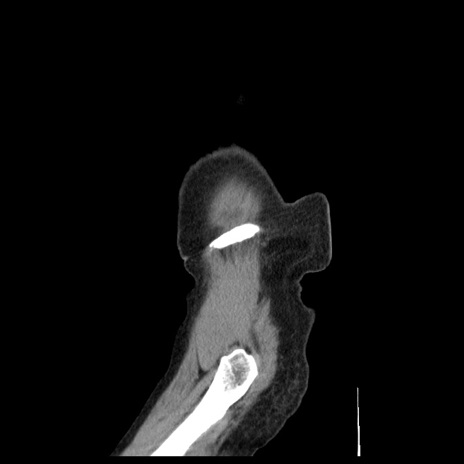

横断像

【症例】80歳代女性

【主訴】腹痛

【現病歴】8時間前から腹痛あり来院。

【既往歴】糖尿病、脂質異常症、子宮体癌にて子宮全摘術

【身体所見】意識清明・会話良好だが腹痛で苦悶様、全腹部にわたって反跳痛と圧痛あり

【データ】WBC 13600、CRP 0.14、LDH 224、CK 90